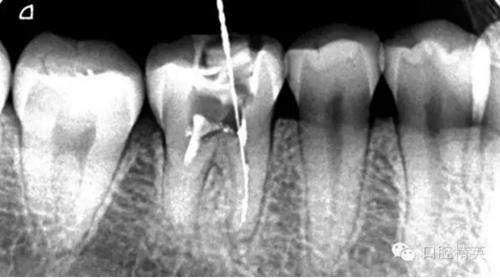

近頰為疏通。慢慢找點(diǎn)可下,近頰花費(fèi)一小時(shí)。